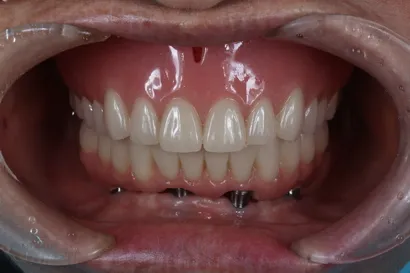

入れ歯からの全顎インプラント治療

60代 男性

執刀医 Dr.大杉 治療内容 他院で製作した入れ歯が「食べにくい・話しにくい・外れる」とお悩みで来院された患者様です。上顎は4本のインプラントで入れ歯を支える「オーバーデンチャー」としました。上あごを覆う部分をなくせるため、発音や食事がしやすくなります。下顎は「オールオン4」で歯をしっかり固定し、機能的に大変ご満足いただけました。

上顎:インプラントオーバーデンチャー(インプラントを支えにした義歯)

下顎:ピンクポーセレンを用いたチタンフレーム入りのフルジルコニアインプラントブリッジ治療期間 1年 費用 上顎:210万 税抜

下顎:330万 税抜リスク インプラントオーバーデンチャーを固定している連結部分の部品(ゴムなど)は、毎日のご使用で少しずつすり減る消耗品です。緩みの原因になるため、定期的なメンテナンスで状態をチェックし、必要に応じて交換していきましょう。 -